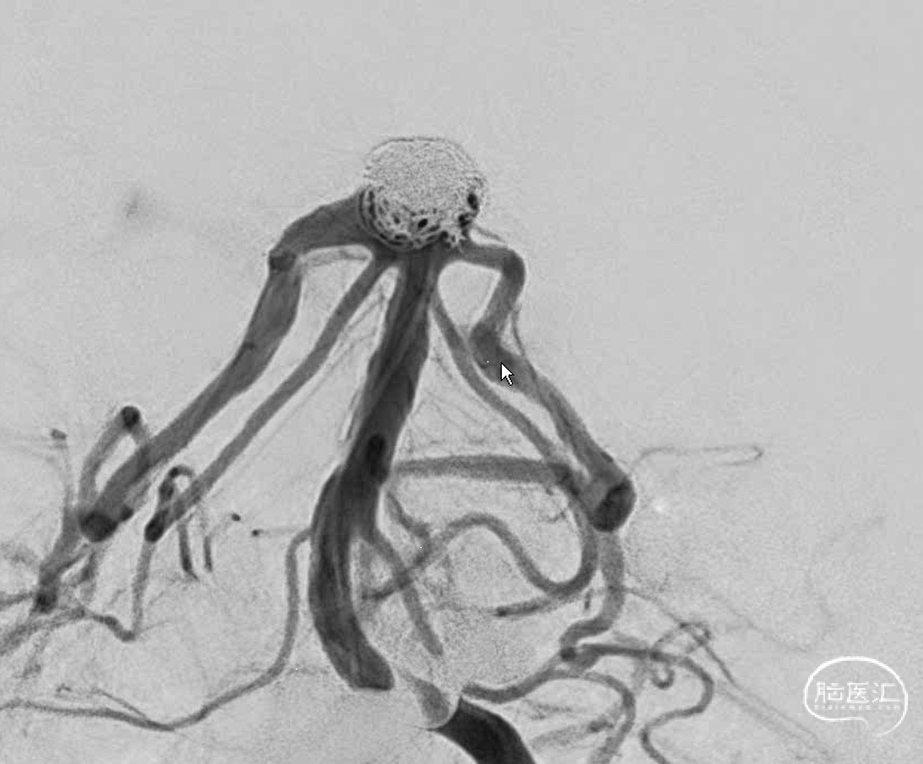

“又是它,大大的瘤,宽宽的颈,实则像个水母”。

虽然棘手,但是也得设计,一个未破裂的动脉瘤。家里比较积极,那就做吧。但是得清楚越安全越好,毕竟没有症状。不管用一个还是两个支架,一切按Y型支架准备。于是乎,双鞘给上。考虑到以往经验,按照自己怎么方便怎么来,右侧鞘安排6F导引导管,操作方便,可以放支架,填弹簧圈。左侧鞘就放个5F导引导管吧,放个支架就完事。

左侧为主椎,当然把6F导引导管放到左侧(黑色箭头),右侧椎稍微细一些,安排上5F的导引导管(红色箭头)。因此右侧大脑后的支架导管塑型角度稍大一些弧形,弹簧圈微导管安排S型,左侧嘛?单弯足以。